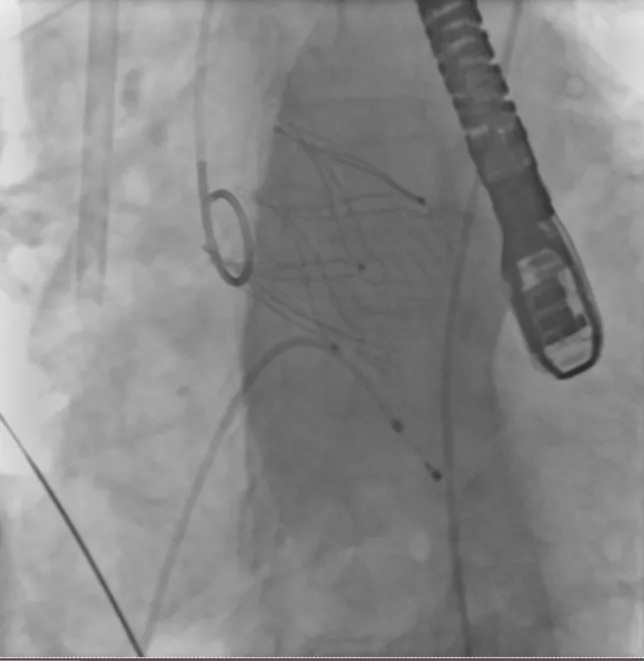

手术纪实:毫米级的生命博弈

2026年3月22日,在国内知名介入心脏病学专家指导下,导管室无影灯下,手术团队以股动脉入路建立“生命通道”。在DSA影像引导下,导丝如“绣花针”般精准穿越血管,将生物瓣膜经导管输送至主动脉根部。随着定位精准释放,新瓣膜如“绽放的花朵”完美贴合,反流即刻消失。